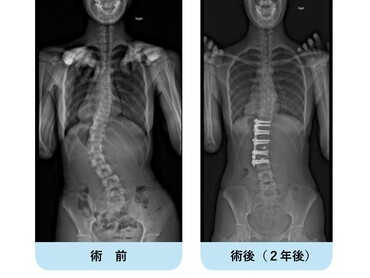

40代の女性です。中学生の時に側弯を指摘されて装具治療を行っていましたが、途中で通院をやめてしまったようです。最近腰痛が顕著となり、仕事や日常生活に支障が出てきたため来院されました。著しい側弯変形を認め、側面では胸腰椎移行部の腰曲がりが既に出現しています。

腰椎側方経路椎体間固定術と後方矯正固定術を2回に分けて行い、下位腰仙椎の固定術を回避して生理的な姿勢、側弯の改善が得られました。腰痛は無くなり、仕事も痛みなく出来るようになりました。

40代の女性です。この方も10代の頃に側弯の診断で装具治療を勧められましたが、嫌で通院しなくなってしまったそうです。難治性腰痛で立ち仕事が困難になり、来院されました。著しい腰椎側弯を認め、椎体の形状も既に変形しているのが分かります。椎間板変性に伴う椎体骨棘もあり、背骨の柔らかさが完全に失われて曲がったまま硬く固くなっています。

前方進入による椎体間解離・腰椎側方経路椎体間固定術と後方矯正固定術を2回に分けて行い、下位腰仙椎固定を回避して全体のバランスを良くすることが出来ました。側弯は著明に改善、腰背部の出っ張り・腰曲がりが治っています。このように近年は下位腰仙椎機能を保ちつつ、壮年期特発性側弯症遺残変形を治療しています。